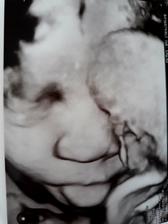

Nase tretie kuriatko😘😙💜